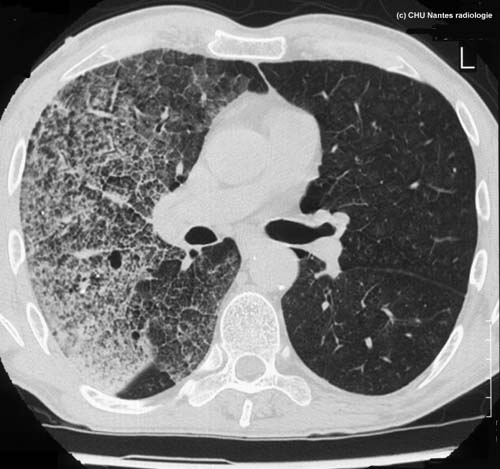

Syndrome interstitiel en rayon de miel : coupe TDM

TDM